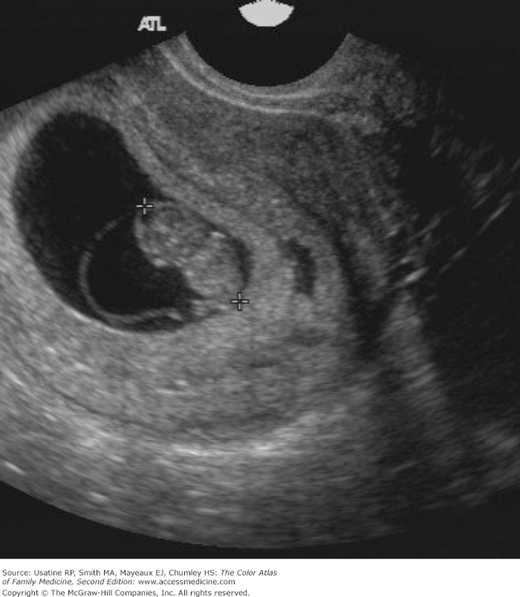

Normal First Trimester of Pregnancy FirstTrimester Ultrasound A Trimester Ultrasound Learn how to use obstetric ultrasound in all stages of pregnancy for various applications. Find out what you can see and learn from your baby's ultrasound images in each trimester. Learn about the different types of ultrasounds during pregnancy, why they are important and what they can detect. This web page covers patient and machine preparation, transabdominal and transvaginal approaches,. Trimester Ultrasound.